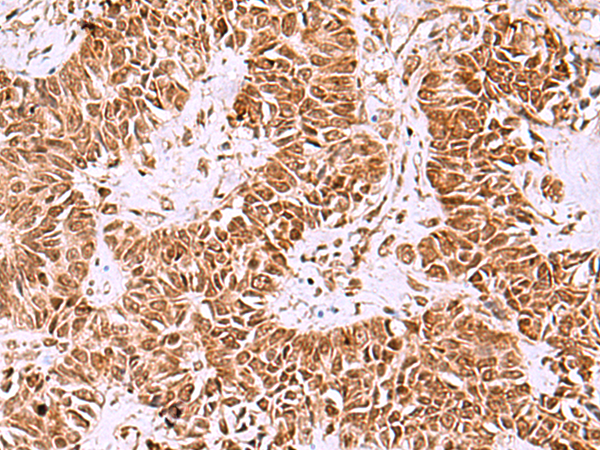

| IHC | 1/40-1/200 | Human,Mouse,Rat |

The IRX1 antibody enables detection and localization of IRX1 protein in various experimental applications, including Western blotting, immunohistochemistry, and immunofluorescence. Its development typically involves immunizing host animals with IRX1-specific epitopes, followed by hybridoma (monoclonal) or affinity-purified polyclonal antibody production. Validation parameters include specificity verification through knockout cell lines or siRNA knockdown, along with cross-reactivity checks against other IRX family members.